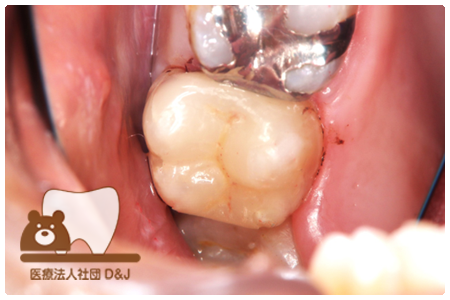

症例3フリジルコニアクラウン 左上6

治療前

治療後

59歳 男性

- 治療内容

- 虫歯で大きく失われた歯に対して、土台としてファイバーコアを使用し、その上にフルジルコニア製の被せ物を装着しました。見た目と強度を両立した自由診療の治療です。

- 治療期間

- 根の治療含めて3カ月半

- 費用

- 自費

フリジルコニアクラウン:77,000円(税込)

(R8.2月時点)

- その他の治療の費用は含まれておりません。

- リスク・副作用

- 強い力が加わると割れる可能性があります。また、噛み合わせや歯ぎしりの影響で脱離することがあります。